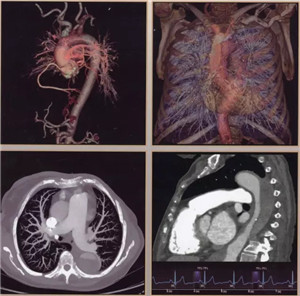

扫描速度超快:仅需0.28秒,不受心率快慢限制,只需一个心跳即完成精准的心脏CT检查,成为无创确诊冠心病的最佳检查手段。

辐射剂量超低:超低的辐射剂量,带来更高清的图像,疾病筛查、儿科、肾功能不全患者也可放心使用。